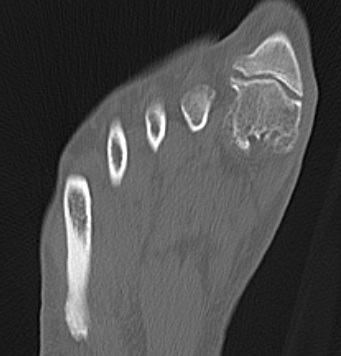

X-ray

Osteoarthritis

- joint space narrowing

- dorsomedial osteophyte

Mild to moderate OA

Severe OA